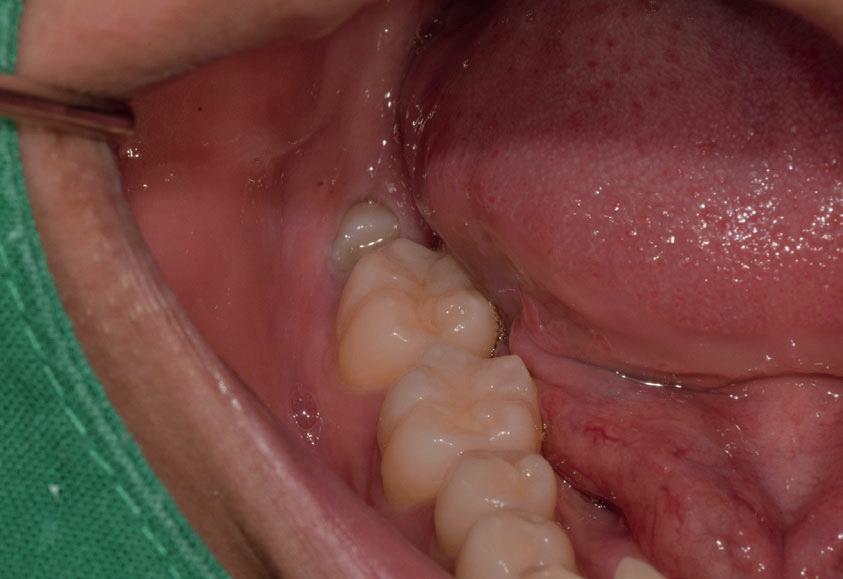

Questo è un paziente di 22 anni ed essendo un amico, ho potuto ben documentare il caso con il suo consenso: il suo dente del giudizio inferiore sinistro è stato estratto utilizzando il manipolo dritto. Figg. 143-149

Figg. 143-149 - Caso 1, paziente di 22 anni: tecnica di estrazione con divisione orizzontale utilizzando il manipolo dritto. Fig. 143 Fig. 144 Fig. 145 Fig. 146 Fig. 147 Fig. 148 Fig. 149